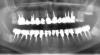

Doc Опубликовано 4 июля, 2009 Поделиться Опубликовано 4 июля, 2009 ВКВ тоже ломаются в основном из за проблем с литьем. Покажите мне сломанную вкладку и я Вам объясню в чем была ошибка доктора. Грамотно сделанная вкладка НЕ МОЖЕТ сломаться!!! Скорее сломаются зубы, корни, все, что угодно вокруг. Вот, например, одна из очень старых работ, когда я еще только начинал читать лекции по вкладкам Это контрольный снимок сделан год назад, я его сейчас показываю, как образец устарелых методов, понятий и изготовления. )) Ссылка на комментарий

Др. Шпульке Опубликовано 4 июля, 2009 Поделиться Опубликовано 4 июля, 2009 (изменено) Покажите мне сломанную вкладку и я Вам объясню в чем была ошибка доктора. Грамотно сделанная вкладка НЕ МОЖЕТ сломаться!!! Скорее сломаются зубы, корни, все, что угодно вокруг. Вот, например, одна из очень старых работ, когда я еще только начинал читать лекции по вкладкам Это контрольный снимок сделан год назад, я его сейчас показываю, как образец устарелых методов, понятий и изготовления. ))Извольте. Изменено 4 июля, 2009 пользователем Др. Шпульке Ссылка на комментарий

Doc Опубликовано 4 июля, 2009 Поделиться Опубликовано 4 июля, 2009 Извольте. Спасибо за снимок. Просто куча ошибок! А можно уточнить, что за коронка, по снимку не совсем понял, это цельнолитая или просто напыленная штамповка, или вкладка с коронокой в одном флаконе? По снимку не совсем ясно. Ссылка на комментарий

Др. Шпульке Опубликовано 4 июля, 2009 Поделиться Опубликовано 4 июля, 2009 Спасибо за снимок. Просто куча ошибок! А можно уточнить, что за коронка, по снимку не совсем понял, это цельнолитая или просто напыленная штамповка, или вкладка с коронокой в одном флаконе? По снимку не совсем ясно.Штамповка с напылением,коронка фиксирована на цемент. Ссылка на комментарий

Doc Опубликовано 4 июля, 2009 Поделиться Опубликовано 4 июля, 2009 Штамповка с напылением,коронка фиксирована на цемент. Хм, ну если забыть обо всех "прелестях" напыленной штамповки, то у этой вкладки следующие проблемы:1. Соотношение высоты коронки и вкладки должно быть один к двум. Даже если у нее отломилась половина ножки, то видно, что там еле-еле один к одному, что привело к расшатыванию конструкции и ее расцементировке. 2. Ножка очень тонкая для такой надстройки, диаметр нужно было делать больше. Если канал узкий или короткий, значит не нужно было делать вкладку.3. Нет так называемой "антиротационной площадки". Напрочь нет, даже намека. 4. С феруллом проблемы, его просто нет, как и антиротационной площадки.5. На месте перелома очень сложно при таком качестве снимка разглядеть, но кажется есть овальное углубление, что говорит о наличии поры в литье.6. Судя по виду ножки она в устье болталась, как кое-что в проруби, а кончик настолько насмерть заходил в канал, что его даже подтачивали, что считается недопустимым, значит слепок был снят плохо, либо отлита плохо. Такие вкладки нужно не точить пока не сядут, а переделывать. В результате когда верх расцементировался, кончик, всаженный слишком туго, пытался держать всю конструкцию до тех пор, пока не сломался. В общем, это только то, что более или менее ясно видно из представленных снимков. Просто если в литье пора. Литье раньше не всегда гут. Пора в литье это уже совсем из другого разряда проблема! Это проблема кривых рук литейщика, которая никак не имеет отношения к обсуждению достоинств и недостатков различных штифтовых конструкций. Ссылка на комментарий